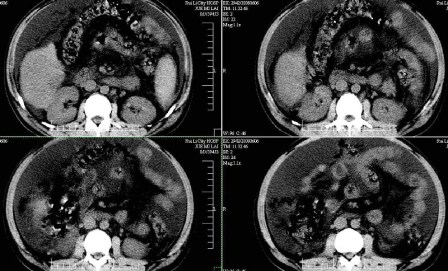

标题: CT13930:M,33岁,腹胀、腹痛10天余。 [打印本页]

标题: CT13930:M,33岁,腹胀、腹痛10天余。

右上腹压痛,肝大,质硬。腹水征。ct:肝右叶(后段)低密度影,性质待定。

肝硬化、大量腹水,肝右叶巨大肿块,境界欠清,中间见不规则低密度坏死区,考虑肝癌应该问题不大,至于肝左叶低密度灶是否转移应该意义不是很大了,慎重起见还是建议增强扫描。

肝硬化、腹水,肝右叶低密度首先考虑肝癌可能,左叶低密度不除外转移可能。建议增强检查。